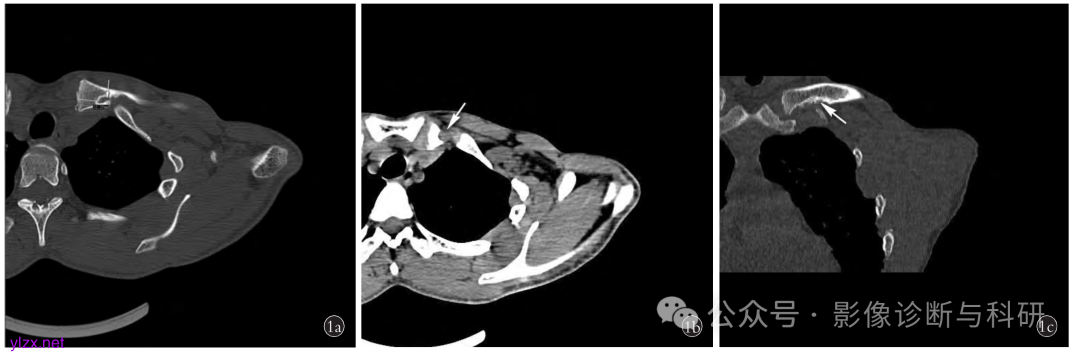

患者,男, 24 岁,锁骨棱形窝 1a. 横断位骨窗示左侧锁骨内侧可见类椭圆形骨质缺损区,锁骨内侧端关节面与病灶内侧缘最近点距离1.2 cm ,缺损区较大,边缘可见硬化,内侧端形态呈鱼钩样(箭头所示) 1b. 横断位软组织窗可见小条状软组织灶伸入(箭头所示) 1c. 冠状位骨窗示锁骨内侧端下缘骨质缺损,边缘硬化(来源于中国骨伤杂志)